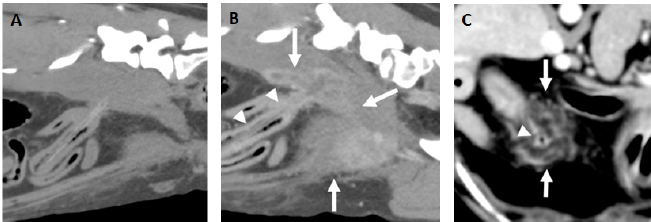

Fig. 2. A and B. Transverse and dorsal, post-contrast CT images (level −500 HU, width 1,400 HU) of the same patient showing a hyperattenuating (112 HU), 63 mm length × 1.3 mm width foreign body (arrowheads) lodged in the right caudal lung lobe and causing a small cavitary lesion (arrow). There is an asymmetric pleural effusion, more severe on the right side (asterisks). The right pulmonary lobes are decreased in volume with an almost generalized consolidation pattern, most likely secondary to atelectasis. C. Parasagittal post-contrast CT image (level −500 HU, width 1,400 HU) of a perforating wooden skewer foreign body from the stomach (arrowheads), perforating the pleural space and right caudal lung lobe which shows a focal increased attenuation and thickening of the visceral pleura. There is a mild volume of pneumothorax (asterisks). Note that the air within the pulmonary cavitary lesions or in the pleural space aids in the identification of these foreign bodies.

When part of the wooden skewer was traversing the pulmonary parenchyma (Fig. 2), the surrounding lung had increased attenuation and the visceral pleura was thickened, features previously described in the perforation site secondary to grass-awn migration and most likely indicative of pneumonia and pleuritis (Baudin Tréhiou et al., 2020). Additional cavitary lesions showing gas-fluid levels with a thin and well-defined wall were present in two dogs. These were interpreted as pulmonary traumatic pseudocysts formed by the retraction of surrounding lung tissue following pulmonary laceration (Cho et al., 2015; Bertolini et al., 2020). Abscess formation could not be ruled out but was considered less likely as usually shows thicker and irregular walls (Lamb and Neiger, 2000). Secondary bilateral and asymmetric pneumothorax was present in all pulmonary perforations, and this asymmetry correlated with the side of the perforation in all cases.